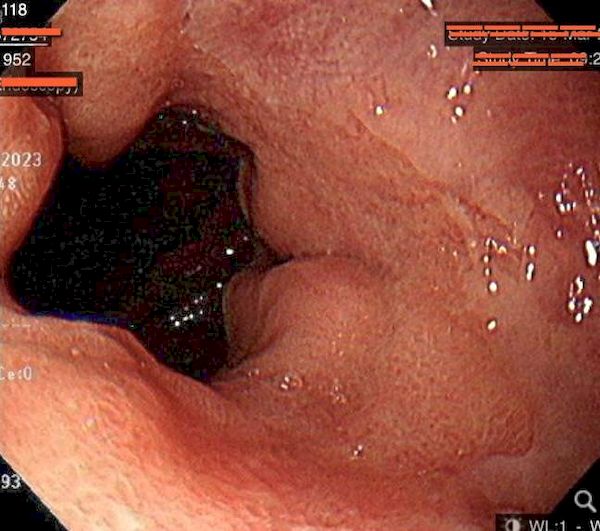

更多一類型患者是聚餐或暴飲暴食後胃腸脹氣脹痛、胃食道逆流掛病號的。近期門診有一對40歲上下的梁姓夫妻,每週有3到4次晚餐必吃麻辣鍋物、燒烤,雙雙因為胃酸過多、胃食道逆流前來就醫,但先生因有抽菸飲酒習慣,有火燒心、吞嚥困難、喉嚨異物感等,症狀較嚴重。圖片說明:梁先生胃鏡檢查發現胃潰瘍